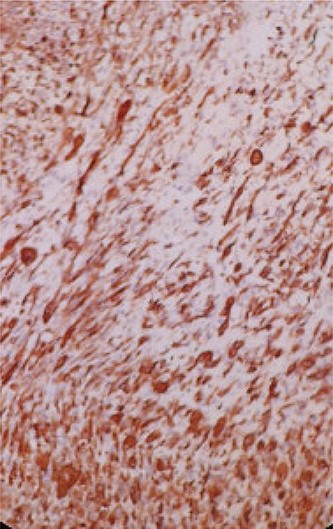

Immunohistochemical (IHC) study shows the positivity of rhabdomyoblastic cells to the anti-desmin antibody (IHC * 20).